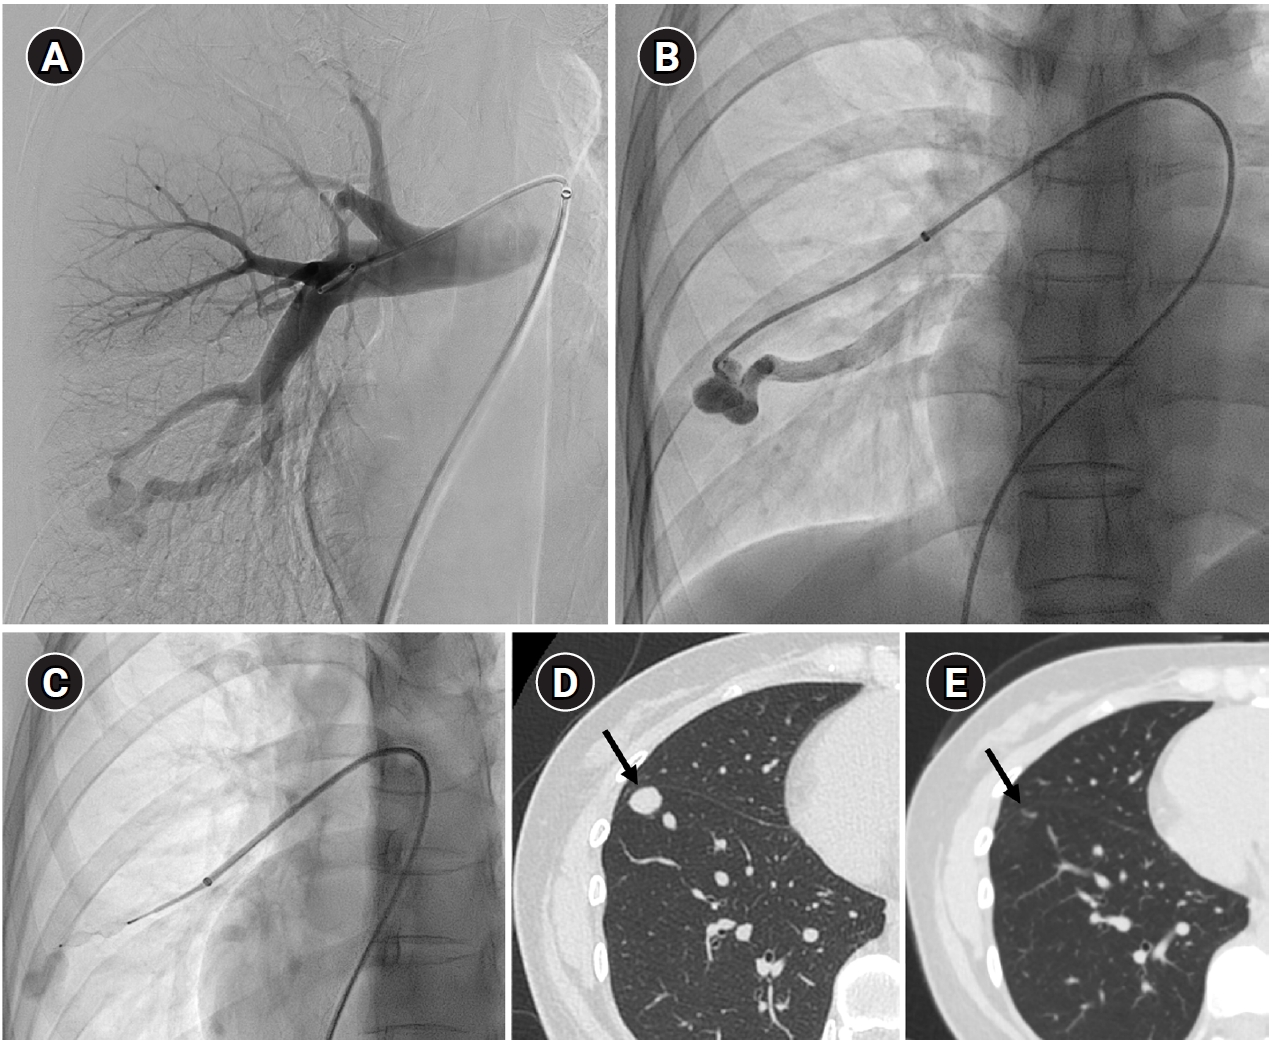

Fig. 8.

Computed tomographic (CT) images of a pulmonary arteriovenous malformation before the procedure (A), 20 days after embolization (B), and at the 6-month follow-up (C). After the procedure, at both 20 days and 6 months, the diameter of the feeding artery and the draining vein is gradually reduced. In this case, the embolization was performed using an Amplatzer vascular plug type IV. Notably, the Amplatzer vascular plug produces minimal beam-hardening artifacts on CT, aiding in the evaluation of vessel diameter and the surrounding parenchyma.

kjir-2026-00010f8.jpg

Long-term follow-up after treating PAVMs is needed to detect newly developed PAVMs and to identify persistence or recurrent flow [10,11]. Treatment failure in PAVMs can be classified as recanalization and reperfusion. Recanalization refers to the reopening of blood flow through spaces between the previously placed embolic material (Fig. 6). Reperfusion, on the other hand, occurs when blood flow from an adjacent pulmonary artery reopens the previously embolized distal vein or venous sac (Fig. 7) [32]. As the primary follow-up modality, CT is recommended, but there are currently no specific guidelines on whether or not to use contrast enhancement [33]. It is recommended to perform an initial evaluation by CT about 6 months after PAVM embolization, and then follow-up with CT every 3–5 years thereafter (Fig. 8). In CT follow-up, the evaluation is based on the reduction rate of the venous sac or the draining vein, and the traditional criterion is that there should be at least a 70% reduction in the size of the venous sac or draining vein [34,35]. In recent studies, there have been opinions that this 70% size reduction criterion is too strict. In response, some research using angiographic-confirmed cases or time-resolved magnetic resonance angiography (TR-MRA) has proposed a 50%–60% guideline [36,37]. When using CT, repeated radiation exposure and metal artifacts from the coils can be problematic. By using metal artifact reduction techniques, it is possible to obtain clear images of the surrounding parenchyma, and this also helps in assessing parameters like the draining vein diameter reduction rate (Fig. 9) [38]. Furthermore, low-dose CT protocols may help reduce cumulative radiation exposure during repeated follow-up imaging.